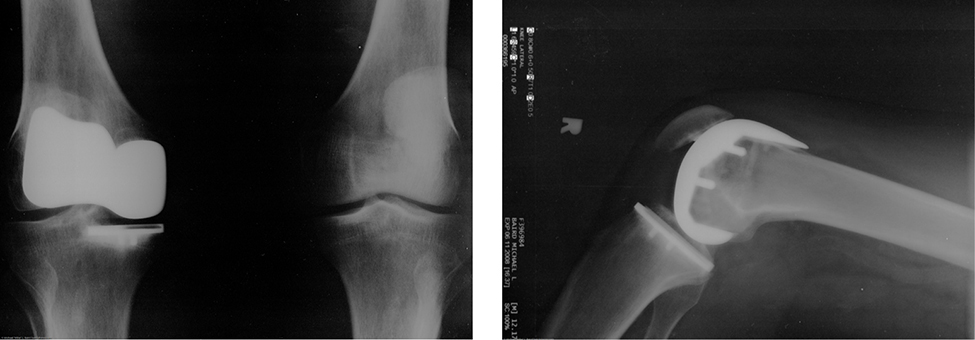

Many people have experienced the slipperiness of walking on ice. However, many parts of the body, especially the joints, have much smaller coefficients of friction—often three or four times less than ice. A joint is formed by the ends of two bones, which are connected by thick tissues. The knee joint is formed by the lower leg bone (the tibia) and the thighbone (the femur). The hip is a ball (at the end of the femur) and socket (part of the pelvis) joint. The ends of the bones in the joint are covered by cartilage, which provides a smooth, almost-glassy surface. The joints also produce a fluid (synovial fluid) that reduces friction and wear. A damaged or arthritic joint can be replaced by an artificial joint (Figure 6.12). These replacements can be made of metals (stainless steel or titanium) or plastic (polyethylene), also with very small coefficients of friction.

Two X ray photos of artificial knee replacements.

Figure 6.12 Artificial knee replacement is a procedure that has been performed for more than 20 years. These post-operative X-rays show a right knee joint replacement. (credit: modification of work by Mike Baird)